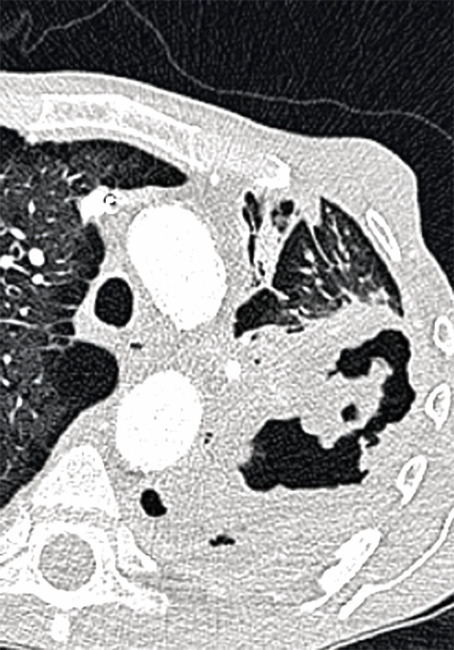

L’ABPA est dite ABPA-S pour sérologique si le scanner est normal, ABPA-B si dilatations bronchiques avec ou sans impactions mucoïdes, ABPA-HAM en présence d’impactions mucoïdes hyper­denses, facteur de mauvais pronostic et d’échec du traitement, et ABPA-CPF devant des signes de fibrose (fig. 1).

L’aspergillome simple (AS ; fig. 2) a l’aspect d’une balle fongique constituée d’hyphes siégeant dans une cavité pulmonaire ou pleurale préexistante ou, plus rarement, dans un foyer de dilatation bronchique. À la radio, c’est initialement un simple épaississement de la surface interne d’une cavité à paroi fine, habituellement au niveau des lobes supérieurs. Aspect typique : image arrondie intracavitaire déclive entourée d’un croissant gazeux.4 L’AS touche des patients immunocompétents. Les manifestations pulmonaires sont rares et discrètes, elles sont liées à l’érosion de la paroi de la cavité par la balle qui peut provoquer une hémoptysie massive.

Contrairement à l’AS, dont la prise en charge est avant tout chirurgicale, l’APC (fig. 3) requiert généralement un antifongique systémique prolongé au moins 6 mois,4 avec parfois un geste chirurgical. Un antifongique à long terme expose aux risques d’interactions médicamenteuses, d’événements indésirables et de résistance.